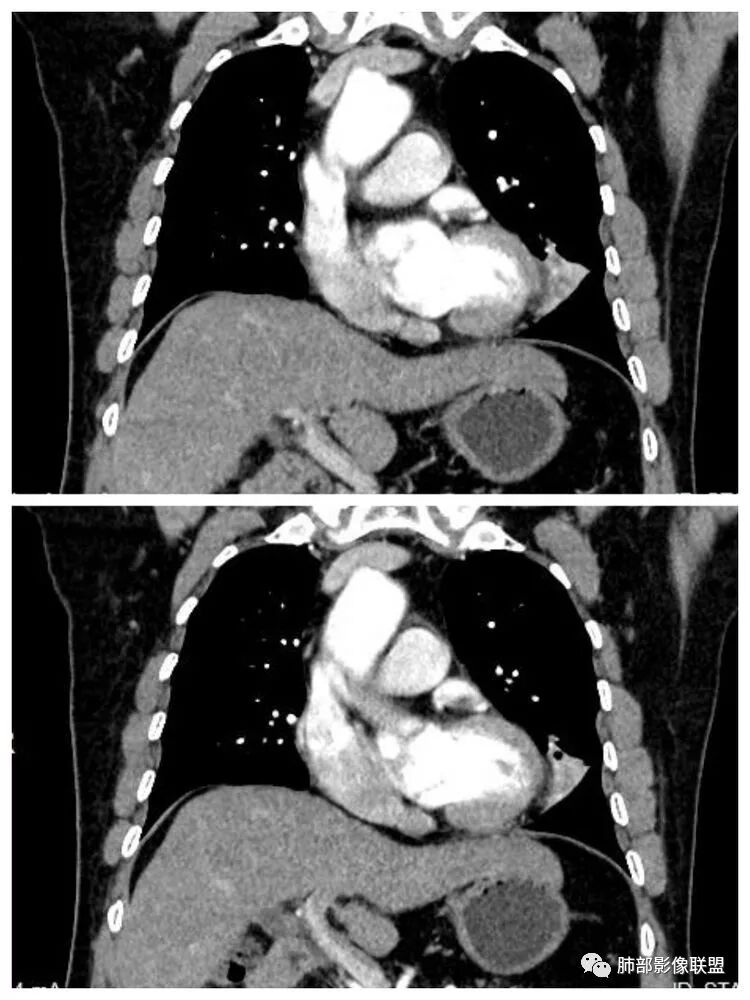

患者,男 ,66岁, “左肺占位”收住院。CEA   5.23 轻度增高

平扫 动脉期 静脉期  40HU、48HU、57HU

患者老年男性,“左肺占位”收入住院。查CEA轻度升高。胸部CT:左肺肺门占位并左肺下叶阻塞性,远端肺组织膨胀不全,增强可见轻度强化,内似见低密度灶。双肺多发类圆形结节,以左肺上叶尖后段为大,内可见部分钙化,边缘光滑、清楚。综合考虑恶性病变,鳞癌并转移可能大,鉴别腺癌、结核。

1.定位:左肺块影同时累及下舌段及下叶内基底段且相互延续。病灶跨叶,或存在叶裂发育异常,或者说就是病灶的肺门蔓延。

2.病灶前上部分与舌段支气管相关且形成阻塞。

4.增强扫描左肺门区块影轻度强化,强化程度轻于舌段周围不张肺组织。

5.双肺门及纵隔未见明确增大淋巴结。

6.分析:男性患者,左肺门区块状影,支气管阻塞,强化不显著,未见淋巴结肿大,更多见于肺鳞癌。难以解释的是下肺病灶的生长方式。

沿肺门或是叶裂缺损孤立发生且蔓延,转移性腺癌似乎可以解释,但占据较大支气管腔就属罕见了。

本例很难首先怀疑转移灶。